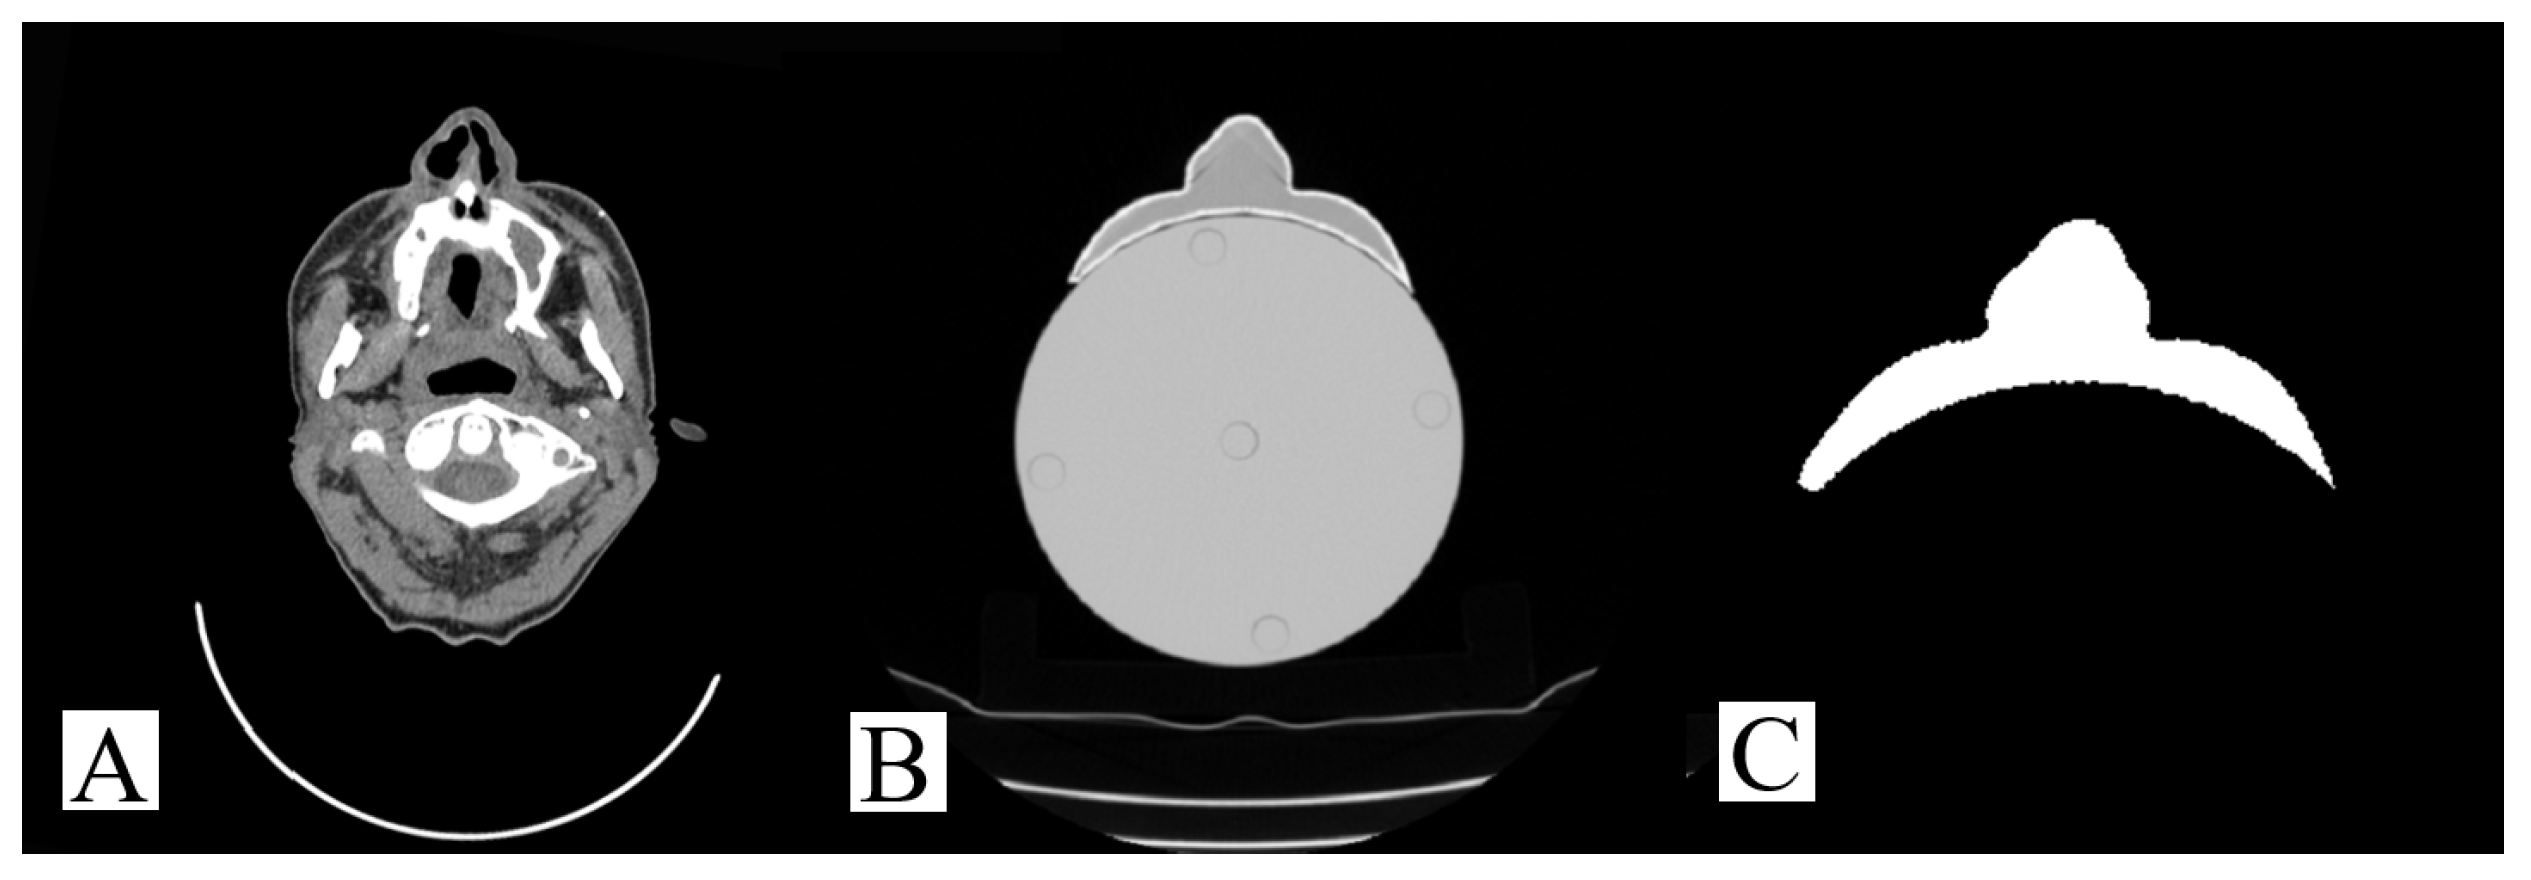

3.2. Conformity of 3D-Printed Bolus